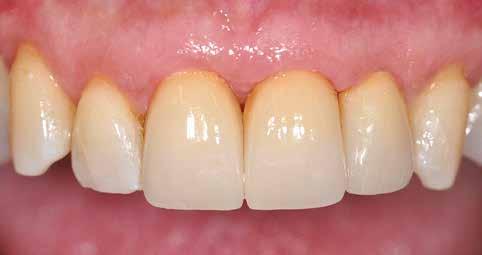

8. ábra: Egyéni ínyformázó titánbázison, tulipán alakú emergenciaprofillal. — 9. a. ábra: A sebzárás okkluzális nézete.

12. a. ábra: Biológiai szélesség 5 mm.

12. b. ábra: Okkluzális nézet négy hónappal a műtét után, amely megfelelő bukkális lágyszövetvastagságot mutat.

13. ábra: Négy hónap elteltével a szájüregben látható marginális zenit megmaradt.

14. ábra: Egészséges implantátum körüli lágyrészgallér.

uni.fit titánalapra (bredent medical). Az implantátum körül a bukkális lágyszövet megfelelő vastagságot és kedvező ínykontúrt mutatott (12. a–b. ábra). Az egyedi ínyformázó eltávolítása után egészséges implantátum körüli lágyrészgallér

volt megfigyelhető (13–14. ábra), ezen kívül közvetlenül a műtét előtt intraorális vizsgálatot végeztünk a lágyszöveti profil megállapítása érdekében. Ezt követte a scanbody behelyezése, így digitális lenyomat készült az implantátum pozíciójáról (15. ábra). Ugyanezzel a technikával rögzítettük az antagonista fogívet és a harapást is. Az így kapott STL-fájlokat digitálisan továbbítottuk a fogtechnikai laboratóriumba. A titánalapra PMMA ideiglenes koronát készítettünk a proximális és marginális illeszkedés ellenőrzése érdekében, valamint a megfelelő harapás elérése céljából (16–17. ábra) Miután az összes igazítás elkészült, ismételt vizsgálatot végeztünk. A végleges hibrid csavarrögzítésű, teljes kontúrú cirkóniumkoronát titánalapon erősen polírozott szubgingivális résszel készítettük el, és 25 Ncm nyomatékra húztuk (18. ábra). Kiváló árnyalategyezést és klinikai eredményt